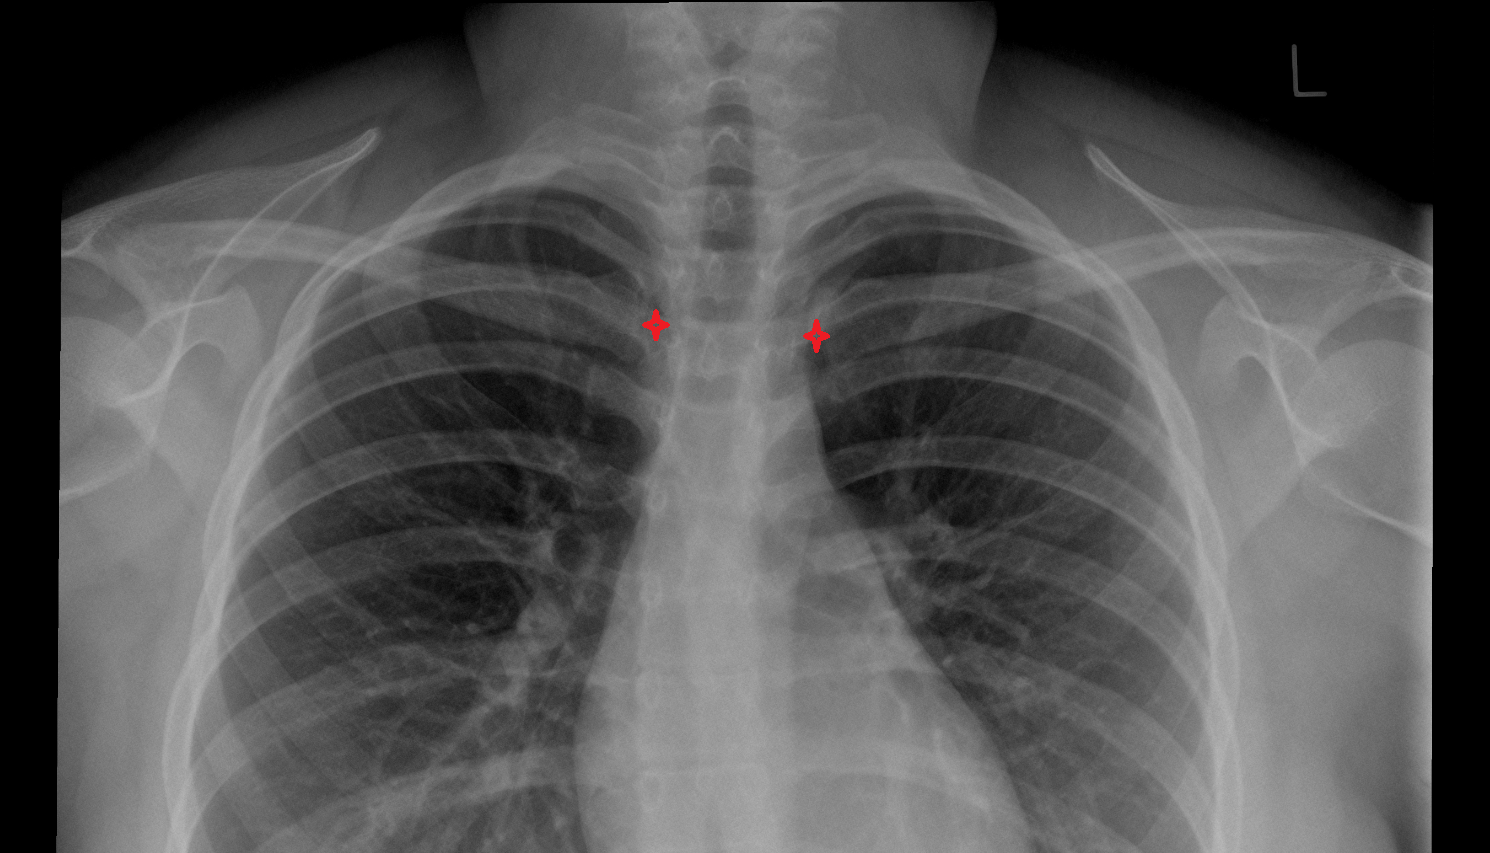

- Carotid bifurcation

- Common carotid artery

- External carotid artery

- Internal carotid artery (cervical part)